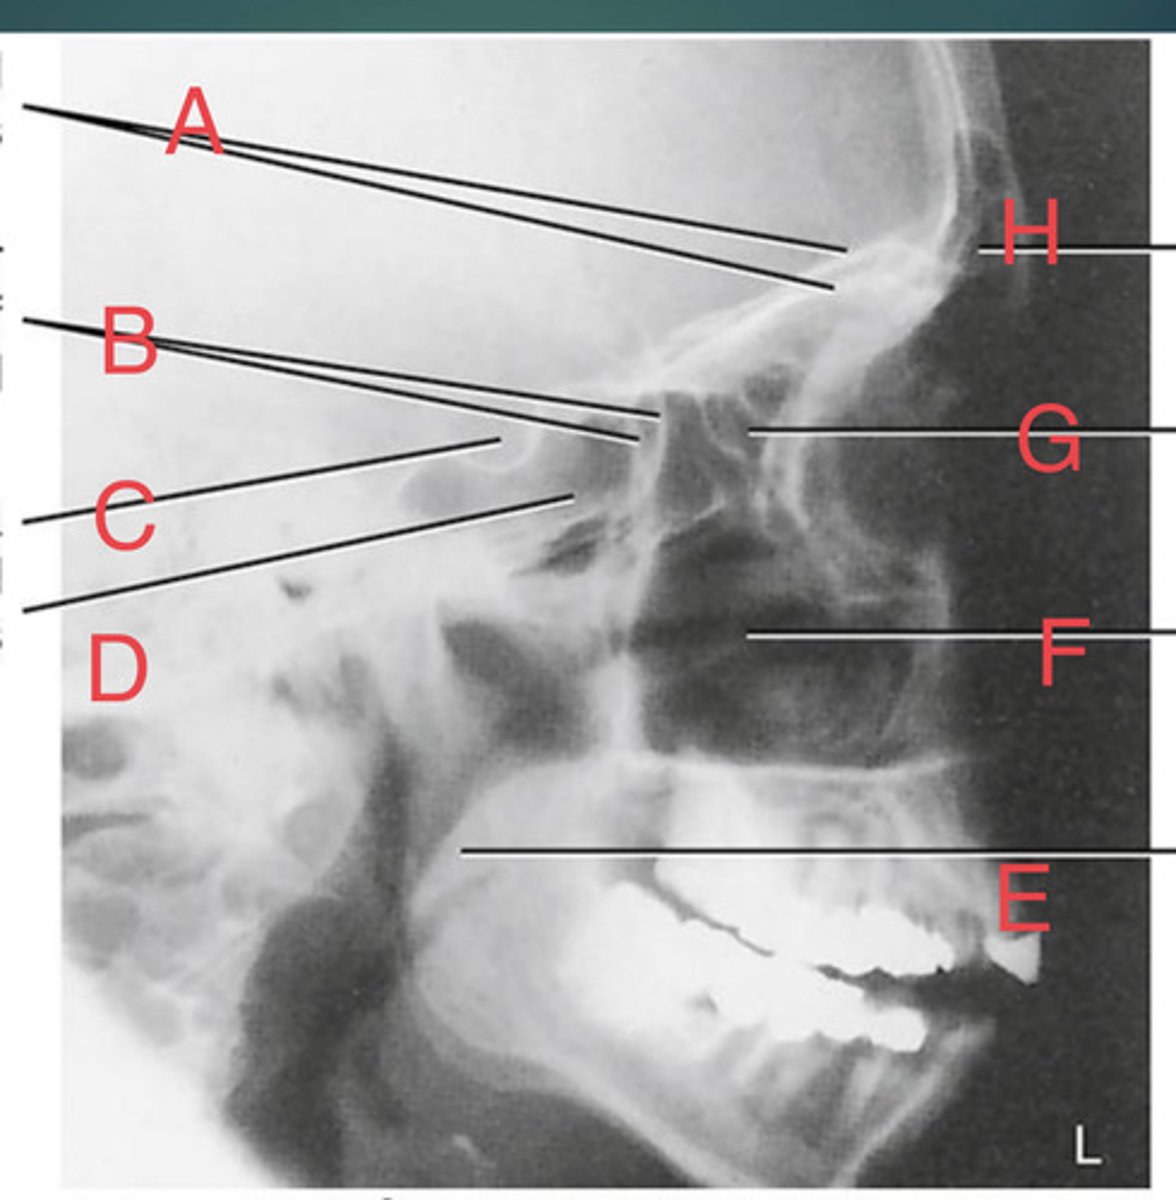

Lateral sinus

What position?

L. Orbital roofs

A.

L. Greater wings of sphenoid

B.

sella turcica of sphenoid

C.

L. Sphenoid sinus

D.

L. Rami of mandible

E.

L. Maxillary sinuses

F.

L. Ethmoid sinuses

G.

L. Frontal sinuses of frontal bone

H.